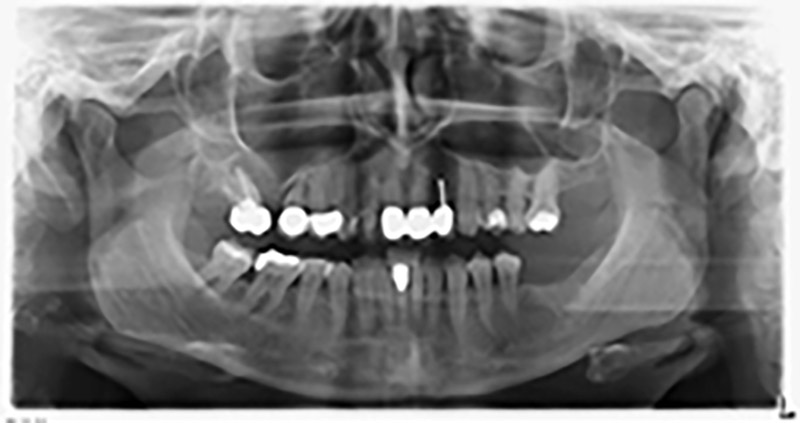

Unos seis meses después de la extracción de las piezas 16 y 14 se realizó una tomografía digital de volúmenes (DVT, Planmeca) para realizar una planificación adecuada y reducir los riesgos al mínimo. En este punto se constató que el hueso no se había regenerado en la cantidad deseada (figuras 2 a 7).

Figuras 2 a 7: Tomografía digital de volúmenes con oferta ósea horizontal reducida.

Con el fin de garantizar una restauración fija en al menos dos implantes, era preciso realizar una elevación del suelo del seno maxilar, tanto en la región 16 como en la región 14. Como en este caso la oferta de hueso residual era extremadamente reducida, fue preciso realizar una retirada ósea relativamente grande. Los procedimientos de retirada ósea grande son invasivos y, además, están asociados a una mayor morbilidad del paciente, llevan más tiempo y resultan más costosos. También es más difícil prever los resultados del tratamiento y el riesgo de fracaso es mayor. Teniendo como telón de fondo estas desventajas, la paciente recibió información sobre la posibilidad de utilizar una alternativa extraíble, pero ella la rechazó firmemente.

Para limitar el aumento a la región 14, se mantuvieron conversaciones con la paciente y se acordó una incorporación oblicua del implante 16 hacia la zona dorso-craneal (figura 8).

Imagen 8: Tomografía digital de volúmenes del ángulo de inserción para el implante 16.